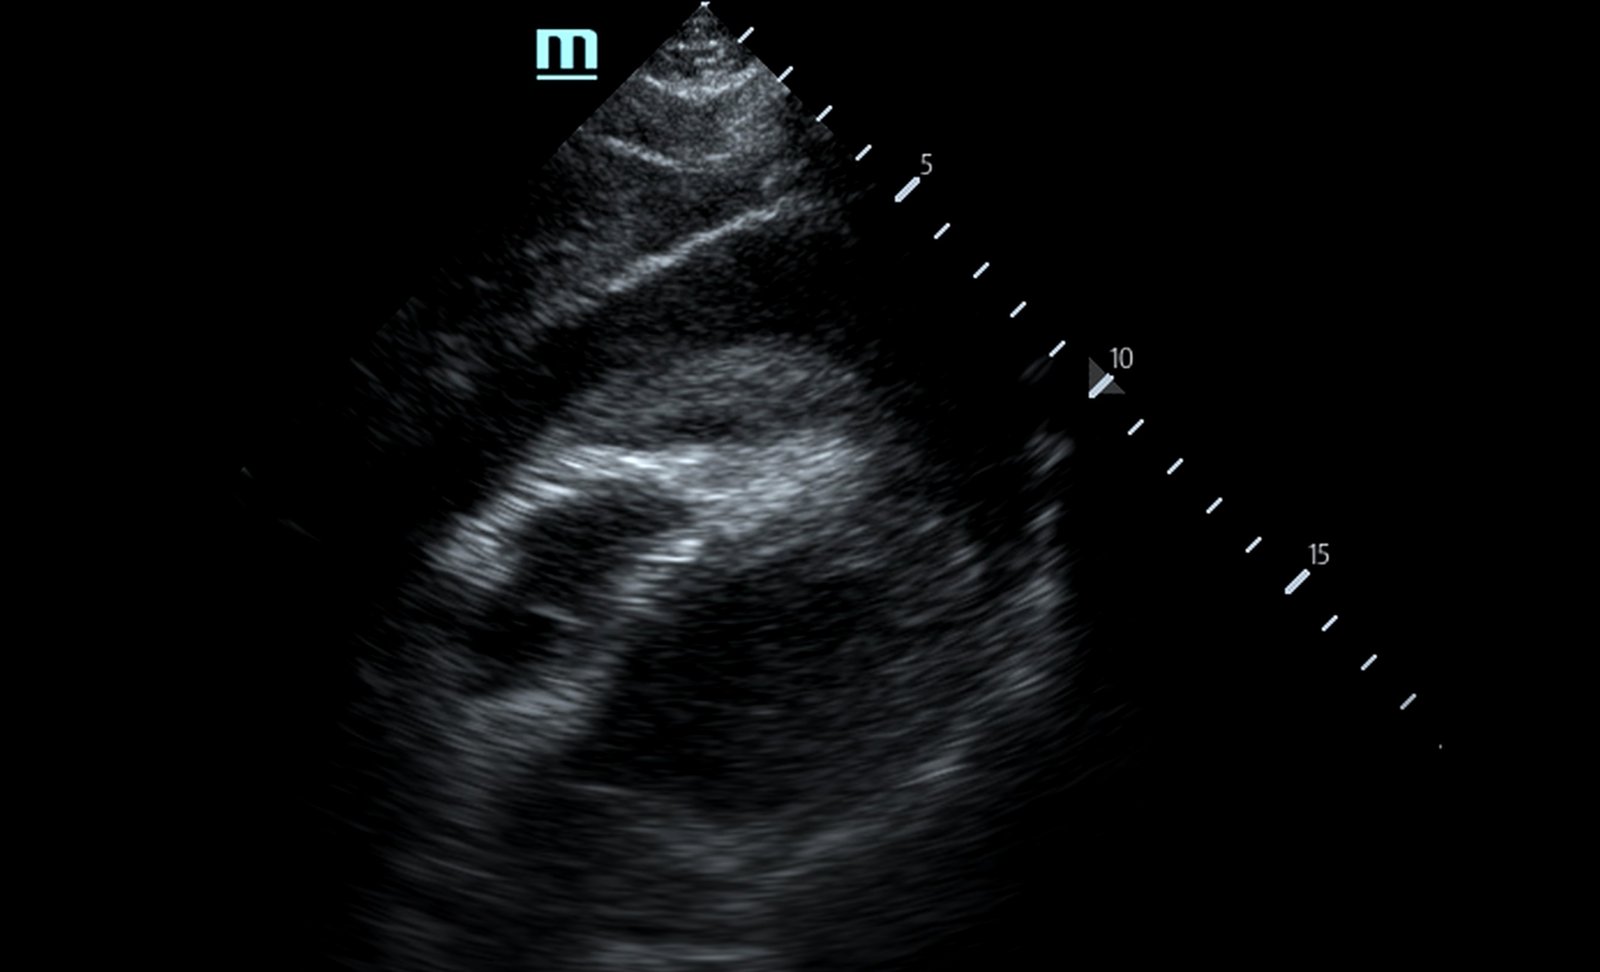

Focused assessment with sonography in trauma (FAST) scan was positive for a clinically significant pericardial effusion as evidenced by the hypoechoic fluid around the myocardium, indicated by the blue arrow in image 2. Findings are also consistent with tamponade process as evidenced by restricted expansion and collapse of the right ventricle during diastole. The hyperechoic floating structure between the pericardium and myocardium, adjacent to the right ventricle, represents a pericardial clot, indicated by the white arrow.The density of the pericardial clot differs from that of the myocardium, thus serving as an additional variable to avoid confusing this as part of the myocardial structure.